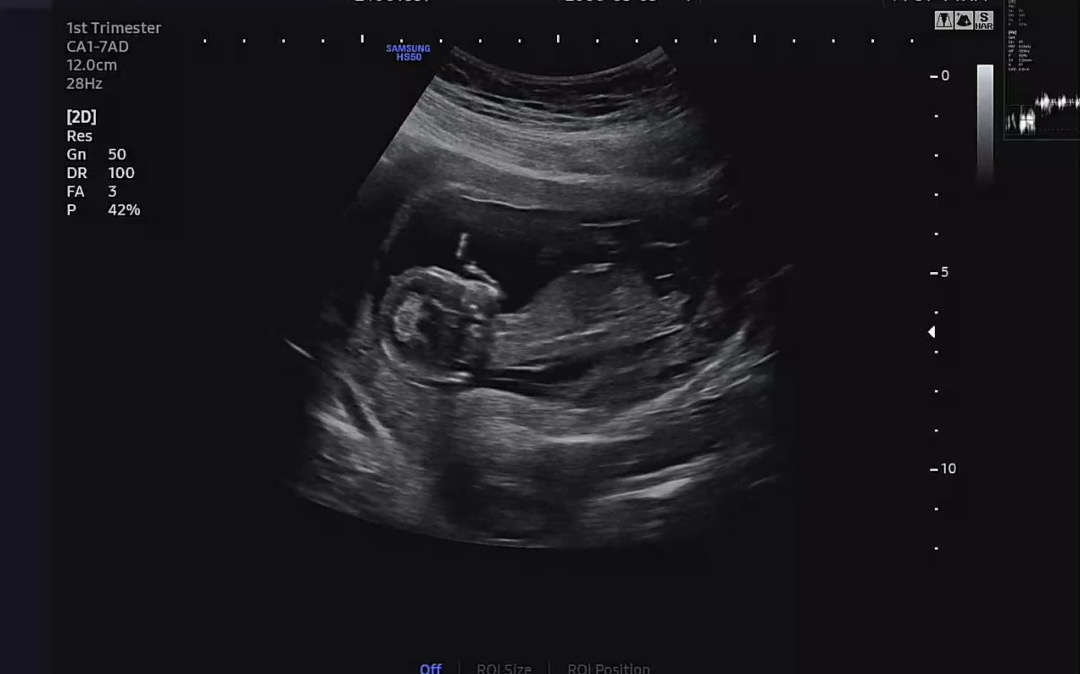

각도법 봐주세용..!

아들인지 딸인지 너무 궁금하네요😭

아들같아요